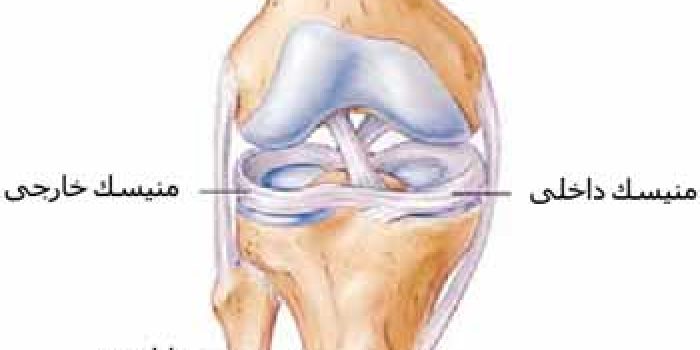

ساختمان دیگر زانو منیسک است. هر زانو دو منیسک داخلی و خارجی دارد که جنس آن شبیه غضروف بوده و مانند بالشتکی در بین استخوانهای ران و ساق قرار میگیرد. وظیفه منیسک ها تسهیل حرکت ران روی ساق است و شوکی را که در هنگام پریدن و راه رفتن به زانو وارد میشود جذب کرده و در واقع با قرار گرفتن بین ران و ساق مانع از این میشود تا این استخوان ها در محل مفصل مستقیما به یکدیگر ضربه وارد کنند.